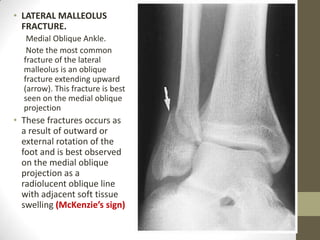

• LATERAL MALLEOLUS

FRACTURE.

Medial Oblique Ankle.

Note the most common

fracture of the lateral

malleolus is an oblique

fracture extending upward

(arrow). This fracture is best

seen on the medial oblique

projection

• These fractures occurs as

a result of outward or

external rotation of the

foot and is best observed

on the medial oblique

projection as a

radiolucent oblique line

with adjacent soft tissue

swelling (McKenzie’s sign)